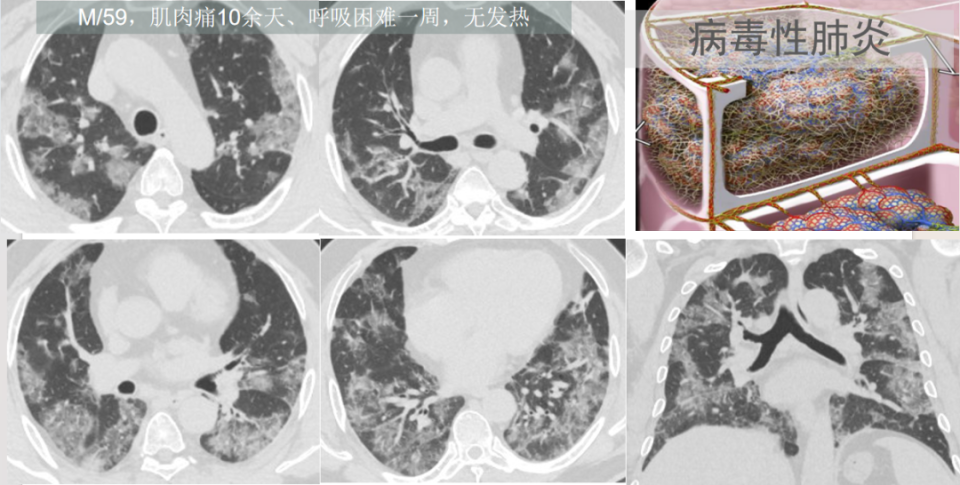

高莉教授:从呼吸科最常见的肺部感染基本影像,谈临床

图片尺寸960x530

我们要想到两个病:在具有流行性和季节性的时候,想到病毒性肺炎的可能

图片尺寸960x485